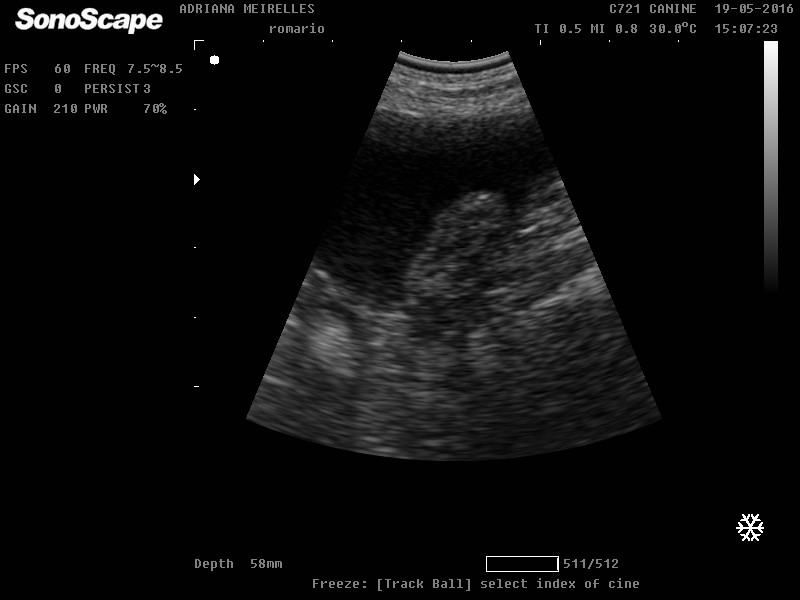

| Bexiga de cão com espessamento e irreguluaridade na porção do trígono vesical. Possível neoplasia. |

| Presença de estrutura oval séssil, sem mobilidade, em parede dorsal de bexiga de cão (possível coágulo, bexiga normal após 7 dias de tratamento com antibiótico). |